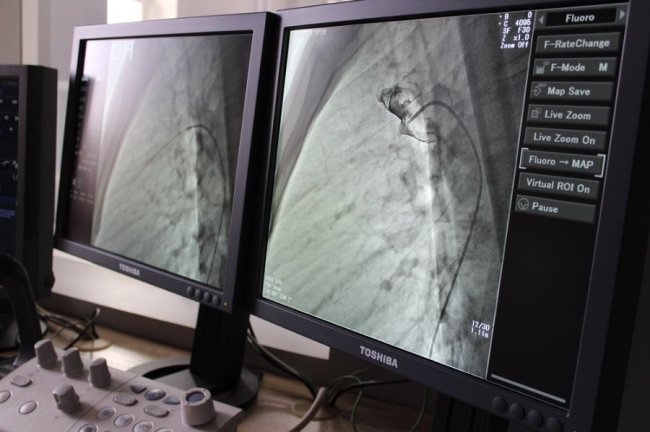

Операція пройшла успішно. Вона була складною. Її проводили під рентгенівським контролем із застосуванням ангіографа, під місцевим знечуленням (без наркозу). Через прокол у стегновій вені і артерії в незакриту протоку встановили оклюдер (маленьку пружинку), яка перекрила потрапляння артеріальної крові у венозне русло.